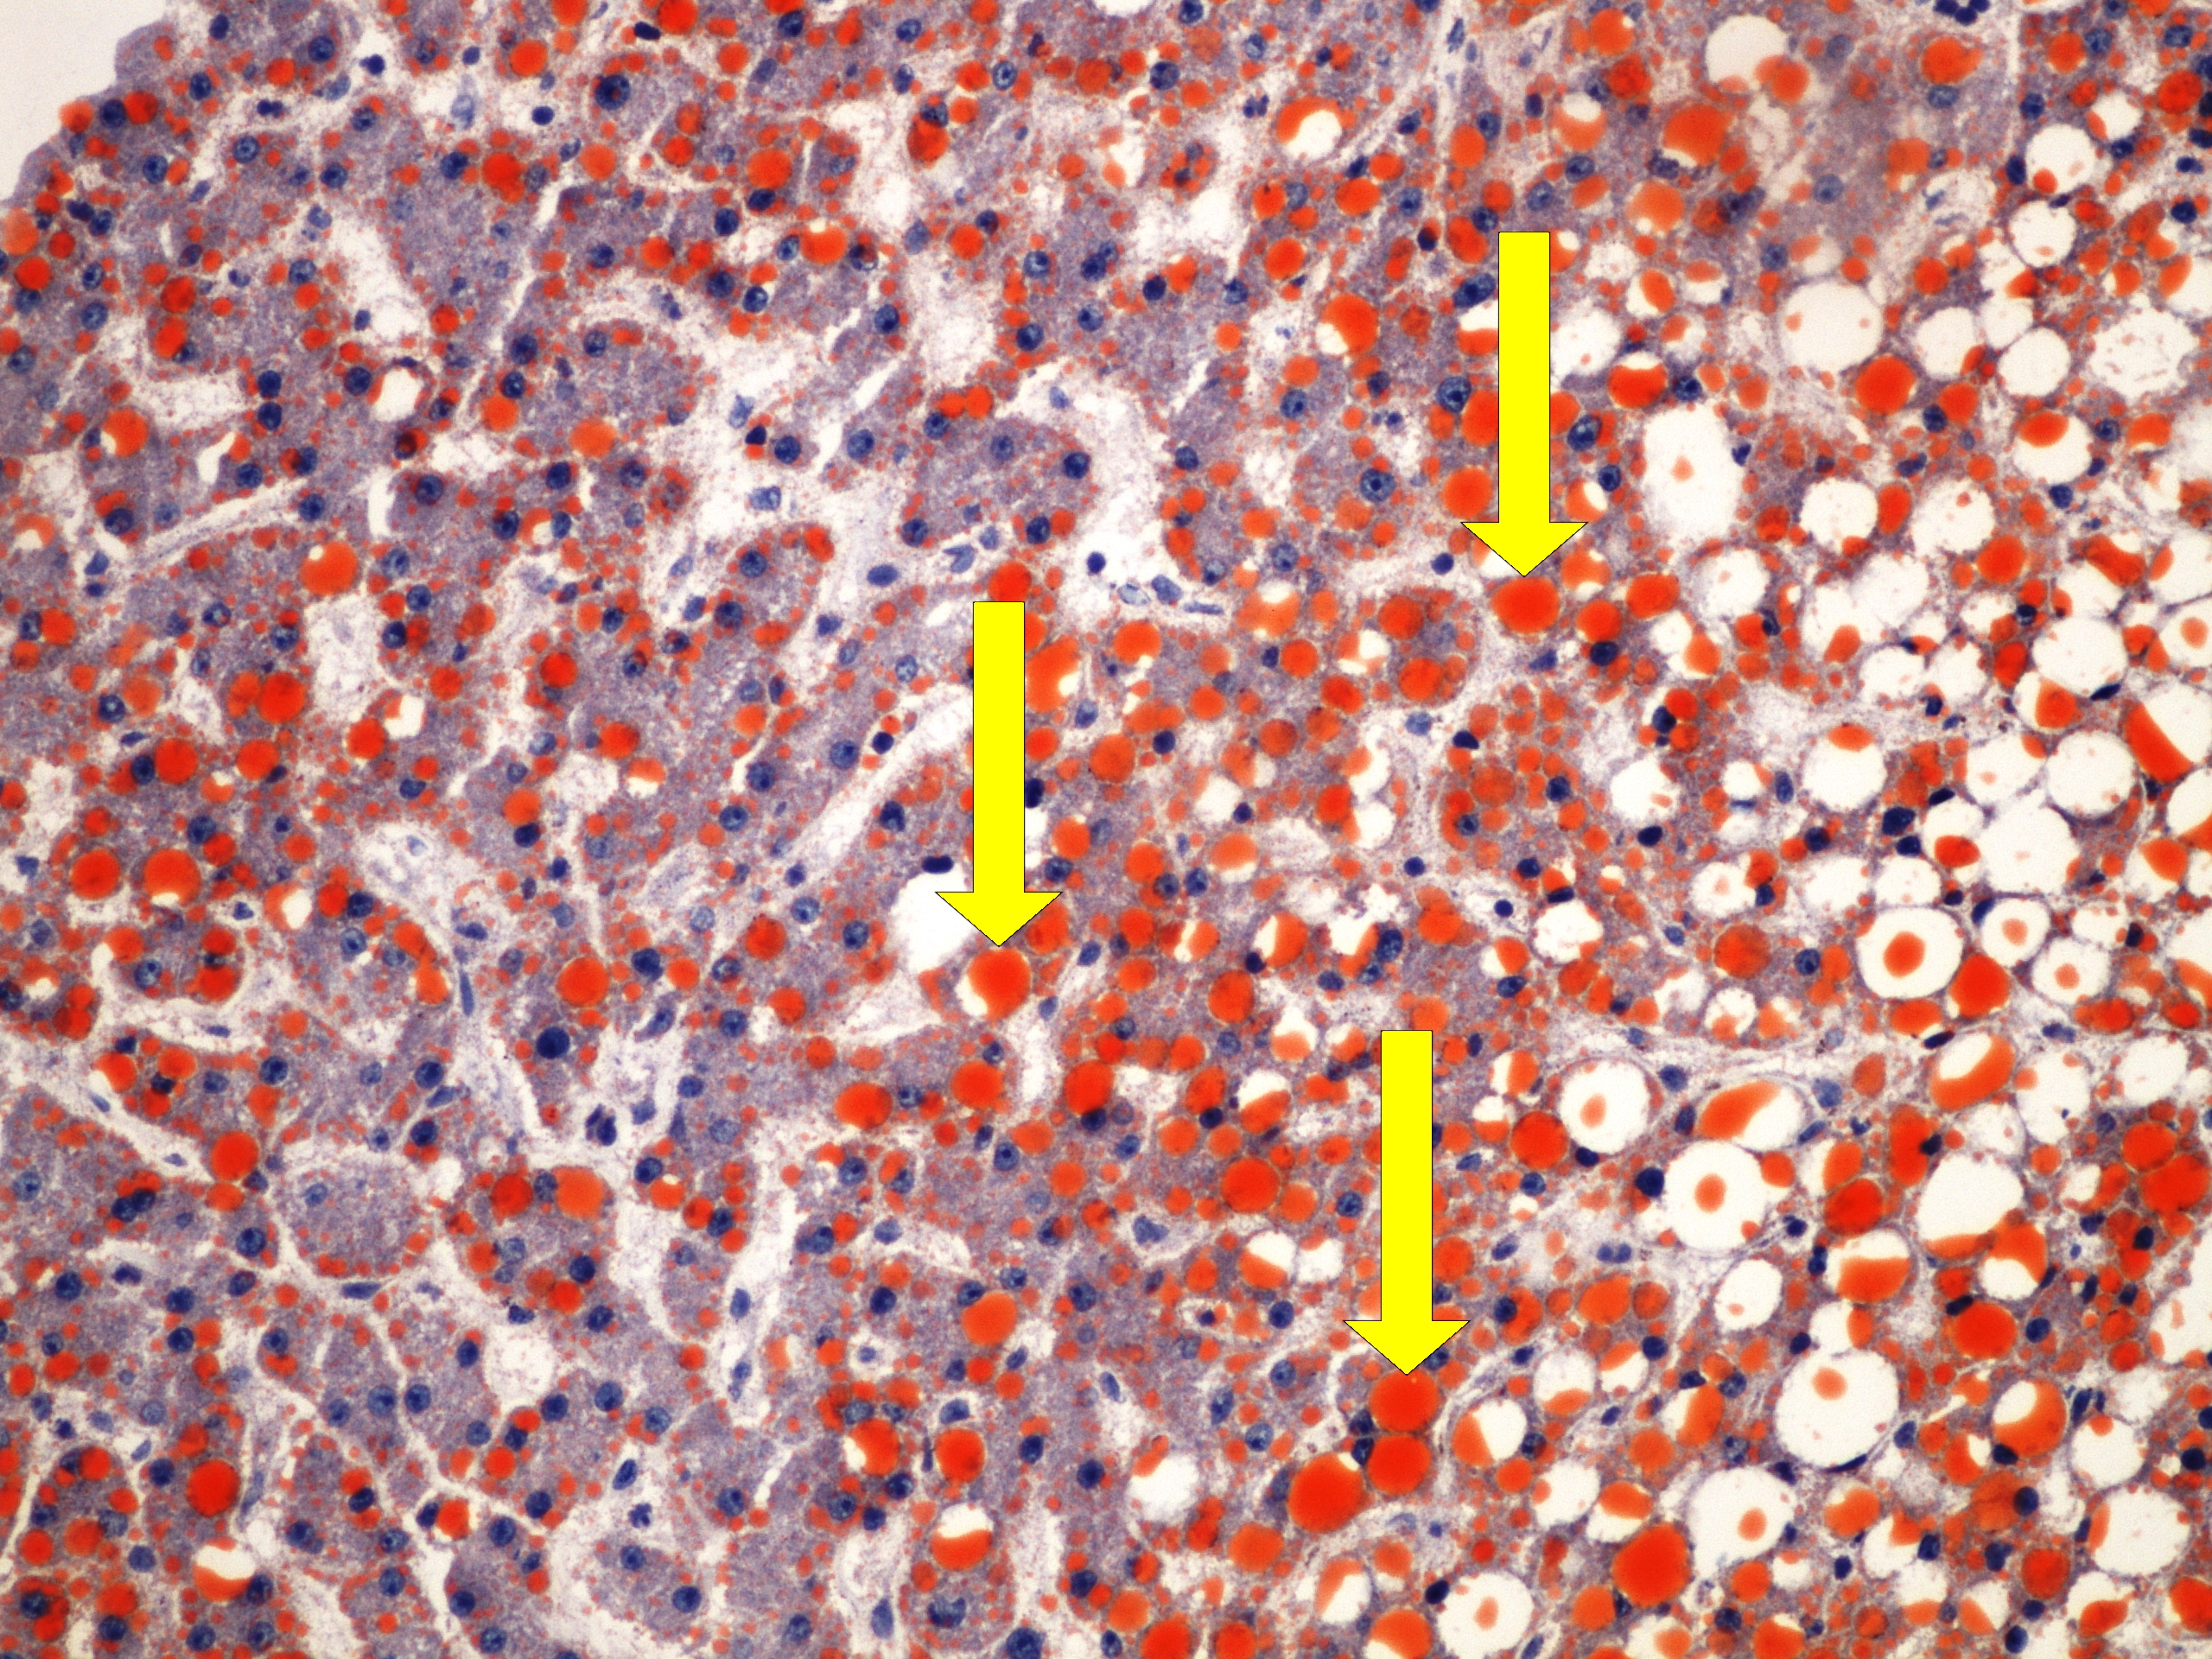

Preparát č.17 a č.18 - barvení PAS (Grawitzův ca)

Struktury

- PAS pozitivní glykogenová zrna v cytoplazmě nádorových buněk